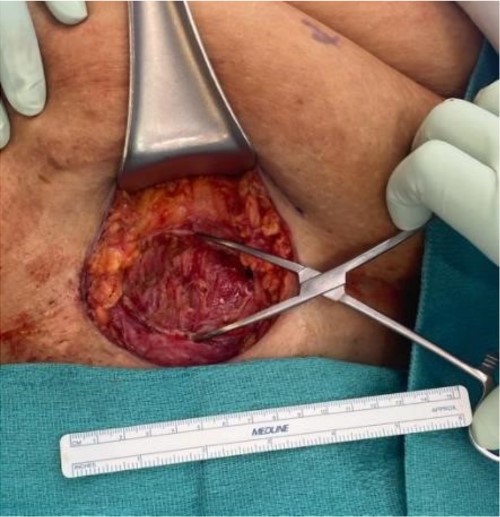

The mass was located in the subcutaneous tissue of the abdominal wall just deep to the previous Pfannenstiel scar and measured 7 × 6 × 4 cm. The mass invaded the anterior rectus fascia without extension into the rectus muscle and was excised en bloc with fascia and grossly negative margins (Fig. 4). Additional margins were excised circumferentially to ensure no further remnant of endometrial cells. The defect measured approximately 12 cm and was closed with synthetic mesh (Fig. 5). Histopathology revealed endometrioma with all margins negative for endometriosis (Figs 6–8). At her postoperative visit, the patient reported complete resolution of symptoms even throughout her most recent menstrual cycle after excision.

Low power view showing endometrial glands and stroma in abdominal wall tissue consistent with endometriosis (H&E).